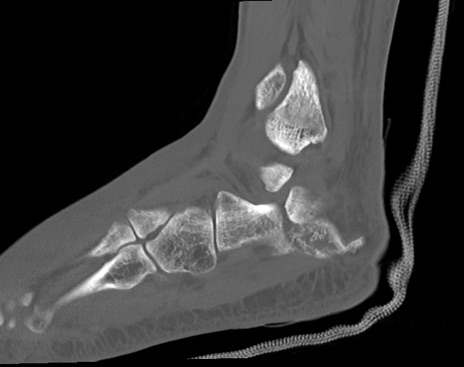

症例37 左足関節CT(矢状断像)

左足関節CT

冠状断像